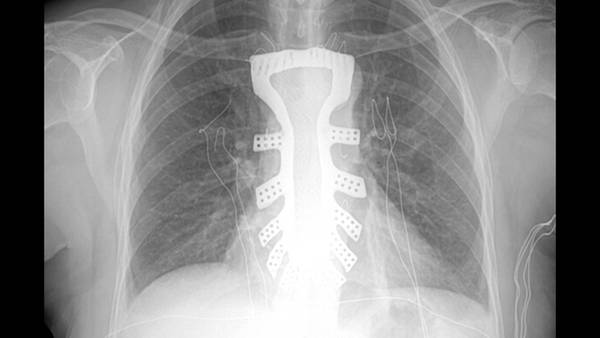

A causa de un tumor en el hueso, los médicos tuvieron que reemplazar el tórax por uno artificial creado a partir de este método, lo que hizo que este trasplante fuera el primero en su tipo en este país asiático, específicamente en el hospital Tangdu de Xian, capital de la provincia de Shaanxi.

Para la sustitución del tórax, los médicos trabajaron mes y medio en el diseño del modelo de platino que sería implantado como el nuevo esternón de la paciente y para lograr este implante, el cuerpo médico pidió la colaboración del laboratorio especializado de la Universidad Politécnica del Noreste, que cuenta con la tecnología 3D.